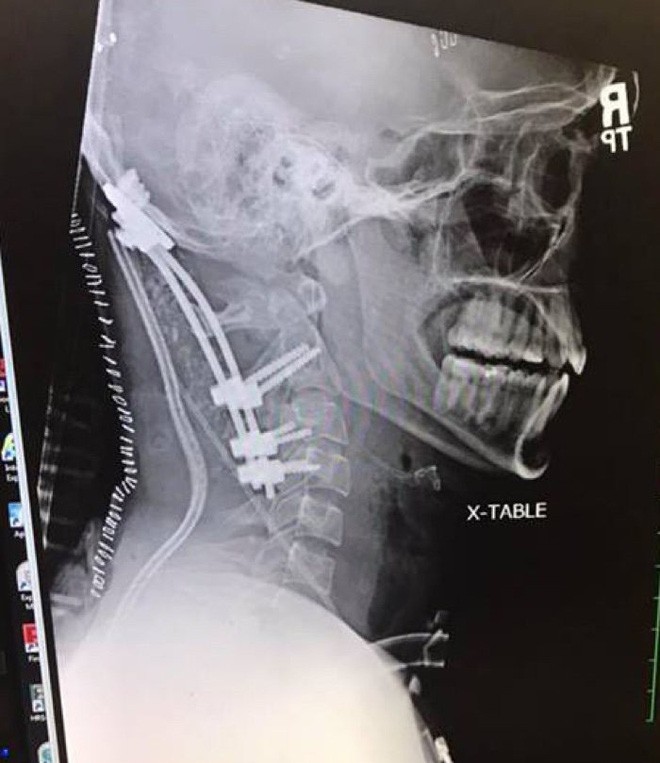

08/08/2018 18:46Chàng trai 22 tuổi gây chấn động y học vì sống sót sau tai nạn 'suýt rụng đầu'

Brock Meister - chàng trai 22 tuổi tại Plymouth (Indiana, Mỹ) là một trường hợp cho thấy số phận đôi khi thật giống một... trò đùa. Bởi vì tùy theo từng góc độ, anh chàng này hoặc là một người cực kỳ đen đủi, hoặc là người vô cùng may mắn.

Cuộc đời của Meister là một chuỗi những bi kịch. Khi mới ra đời, cậu bé Meister đã không thể thở được, lên cơn co giật và chỉ được kéo lại từ tay Tử thần nhờ hồi sức cấp cứu kịp thời. Anh cũng phải dành cả tuổi dậy thì với hóa trị và xạ trị vì chứng ung thư não quái ác.

Nhưng tất cả vẫn chưa là gì so với vụ tai nạn Meister gặp phải vào đầu năm 2018. Vụ tai nạn ấy đã khiến Meister suýt... rụng cả đầu.

Sau này, các bác sĩ đánh giá hành động của người bạn chính là thứ đã cứu mạng Meister. Bởi vì khi nhập viện, các bác sĩ đã phát hiện ra hộp sọ của Meister đã tách khỏi cột sống.

Trong y học, hiện tượng này được gọi là "mất đầu từ bên trong" (internal decapitation).

Theo Kashif Shaikh - chuyên gia giải phẫu thần kinh từ bệnh viện Memorial tại Indiana, thì đây là một trong những trường hợp có tỷ lệ tử vong cao bậc nhất. Thế nên, việc Meister vẫn còn sống quả thực là một kỳ tích gây chấn động giới y học.

Shaikh lý giải, may mắn là việc ngăn không cho Meister ngồi dậy đã giúp anh thoát khỏi cửa tử.

"Đó là giai đoạn nguy hiểm nhất, vì Meister lúc đó giống như một con búp bê, và cái đầu có thể "rụng" bất kỳ lúc nào" - Shaikh chia sẻ.

"Rất hiếm có trường hợp bị như vậy mà sống sót trước khi đến được bệnh viện. Dù vậy nếu nhập viện an toàn, khả năng sống sót sẽ tăng lên đáng kể."

Với trường hợp của Meister, cơ thể anh được giữ cho thật ổn định, gỡ khỏi xe một cách cẩn thận, rồi đặt lên cáng dài và chở đến bệnh viện. Toàn bộ quá trình đó nếu có một sai sót nhỏ thôi cũng đủ để anh vĩnh viễn ra đi.

Nhưng tóm lại thì Brock Meister cũng đã an toàn, dù phải trải qua hàng tháng trời trị liệu. Ở thời điểm hiện tại, anh đã phục hồi khoảng 50% cử động cổ như trước khi tai nạn xảy ra.